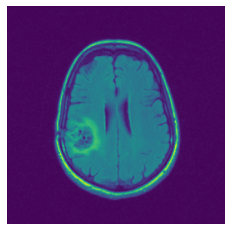

In figure 3, we present qualitative examples of different masking strategies. It is observed that, unlike context prediction and restoration, our method tends to propose targeted masks like the tumor regions or regions with abnormalities and avoids masking less helpful regions. However, it should be noted that Intelligent-Masking does not necessarily mask the tumor regions but considers all areas of interest that results in better feature learning. Examples of other masking samples are provided in supplementary materials. Furthermore, in medical images, unlike natural scenes, the structures are very local with imbalanced information throughout an image. Therefore, random masking strategies as shown in Fig 3 operate ineffectively by masking non-informative regions.

Refer to caption

(a) Original

(b) Intelligent-Masking

(c) Context Prediction

(d) Context Restoration

Figure 2: Qualitative examples of compared method’s strategies for masking